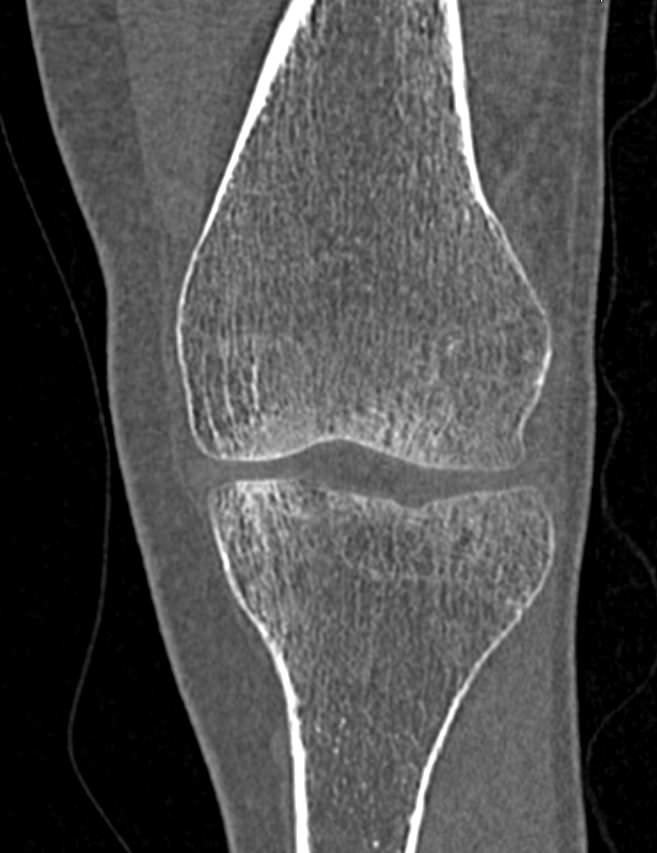

Одним из наиболее информативных методов исследования коленных суставов является мультиспиральная компьютерная томография. КТ относится к лучевым методам исследования и основана на применении ионизирующего излучения с последующей цифровой обработкой данных, полученных при КТ-сканировании.

В наших медицинских центрах обследование коленного сустава проводится на современных мультиспиральных компьютерных томографах последнего поколения TOSHIBA AQUILION. При помощи рентгеновских лучей аппараты послойно сканируют в разных плоскостях исследуемую область с толщиной среза от 0,5 мм. В результате получаются детальные снимки и цифровые трехмерные изображения коленного сустава в мельчайших подробностях. Помимо точности и достоверности диагностики современные компьютерные томографы обеспечивают для пациента минимальную дозу рентгеновского облучения.

Мультиспиральная компьютерная томография дает возможность оценить структуру костной ткани, выявить переломы, воспалительные изменения, участки деструкции костей и диагностировать опухолевые образования. Мультиспиральная КТ часто применяется в ортопедии и травматологии. За счет быстроты, доступности и неинвазивности (то есть обследование выполняется без вмешательства в организм) метод незаменим при травмах сустава, а также при планировании оперативных вмешательств, например, в случае эндопротезирования сустава. В послеоперационном периоде КТ помогает оценить эффективность проведенной операции, вовремя выявить осложнения и отследить процесс восстановления.

Что показывает КТ коленного сустава

- переломы костей;

- артроз;

- артрит;

- скопление жидкости в суставе;

- кисту Бейкера;

- костные наросты на поверхности сустава;

- новообразования

- полные или неполные вывихи — по смещению образующих сустав элементов относительно друг друга;

- деформирующий остеоартроз, ревматический полиартрит

- злокачественную или доброкачественную опухоль

- гемартроз

- абсцесс.